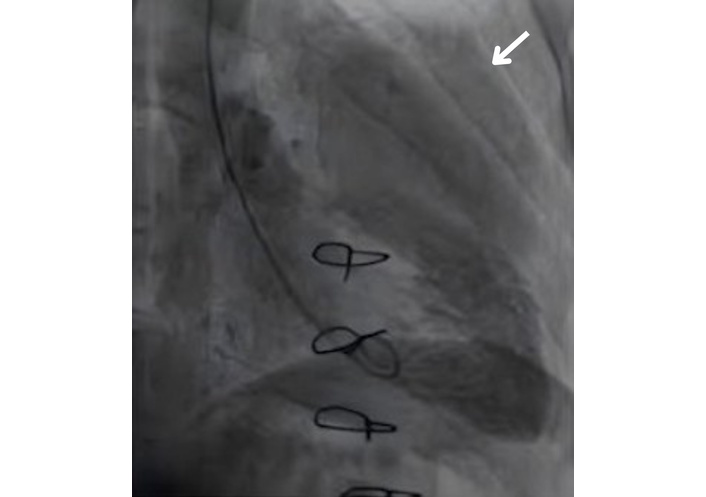

A TTE evaluation performed three months later did not report the mass seen on CXR as a possible pseudoaneurysm (Figure 4). The mass on the left side became more prominent on CXR (Figure 5), nineteen months later. A thoracic CT scan revealed a giant pseudoaneurysm on the posterior wall of LV which was 10 cm × 7 cm in size (Figure 6). The patient was urgently transferred to our center for definitive management, where a coronary angiography (CA) was performed. CA showed normal coronary anatomy (Figures 7 and 8), but left ventriculography confirmed the diagnosis: leakage of contrast medium into the pseudoaneurysm sac was clearly observed (Figures 9 and 10).

Thoracic CT imaging shows a left ventricular pseudoaneurysm (arrow). CT: computed tomography.